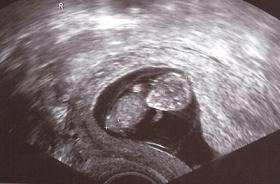

1,3% mehr Schwangerschaftsabbrüche im ersten Quartal 2010